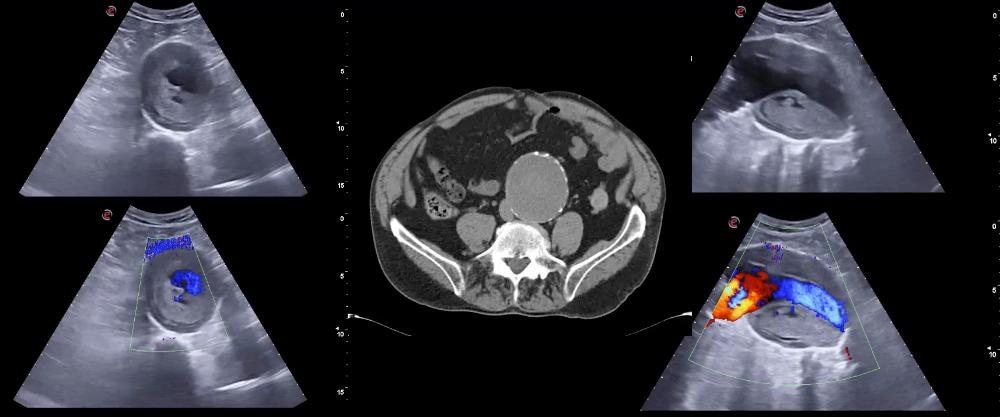

La ecografía se ha convertido en una prueba de imagen esencial en múltiples especialidades médicas distintas de la Radiología (Cardiología, Ginecología, Urología, Anestesiología, Cirugía Vascular, etc.). En los últimos años se han desarrollado ecógrafos de gran calidad, relativamente asequibles desde el punto de vista económico, muchos de ellos portátiles, que permiten realizar exploraciones a la cabecera del enfermo. Estos ecógrafos, como el estetoscopio, el oftalmoscopio, el otoscopio o el martillo de reflejos los puede utilizar cualquier médico. En el campo de especialidades como Medicina Interna y Atención Primaria, la incorporación de la ecografía en la clínica posiblemente ha constituido el procedimiento más importante desarrollado en los últimos 100 años y el único avance tecnológico relevante en el arte de la exploración física desde la invención del estetoscopio.

Se puede definir la ecografía clínica como la exploración ecográfica realizada por el médico directamente responsable del paciente. Es decir, por el facultativo que realiza la historia clínica y máximo responsable del proceso diagnóstico y terapéutico del enfermo. Esta circunstancia supone un valor añadido con respecto a las ecografías regladas que se hacen en los servicios centrales (ej: radiología, cardiología) en las que la información clínica del paciente puede ser escueta y limitada. Por otra parte, la ecografía aumenta de forma considerable la rentabilidad de la exploración física tradicional y mejora sustancialmente el proceso diagnóstico y de toma de decisiones en medicina.

En la ecografía clínica es esencial que la exploración se realice en el punto de atención (a la cabecera del paciente: “point of care ultrasound”). De esta forma se evita el desplazamiento del enfermo al lugar donde se ubica el ecógrafo como sucede en los servicios centrales. Esto supone una mayor comodidad para el paciente, especialmente si está inestable. Otra característica relevante de la ecografía clínica es que puede repetirse todas las veces que el médico lo considere necesario. Así podemos “monitorizar” la evolución de la enfermedad en múltiples circunstancias (congestión pulmonar y derrame pleural en la insuficiencia cardiaca o en pacientes con sobrecarga de volumen, ascitis, derrame pericárdico, condensación neumónica, etc.).